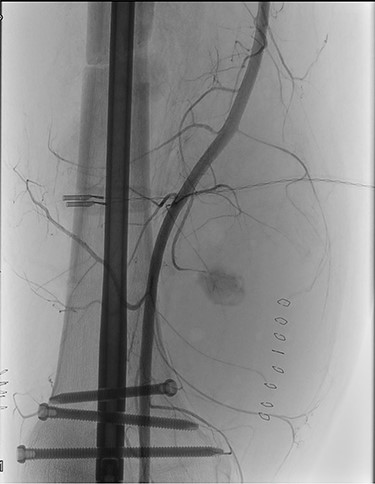

During hospitalization, the patient underwent many orthopedic surgeries for various fractures of the right lower limb, and a centimetric pseudo-aneurysm of the right SFA (Fig. 1), was found at a routine duplex ultrasound of the lower limbs, originating from a small collateral branch of SFA at the distal third of the thigh.

Preoperative angiography showing the pseudo-aneurysm of the right SFA, originating from a small collateral branch of SFA at the distal third of the thigh.